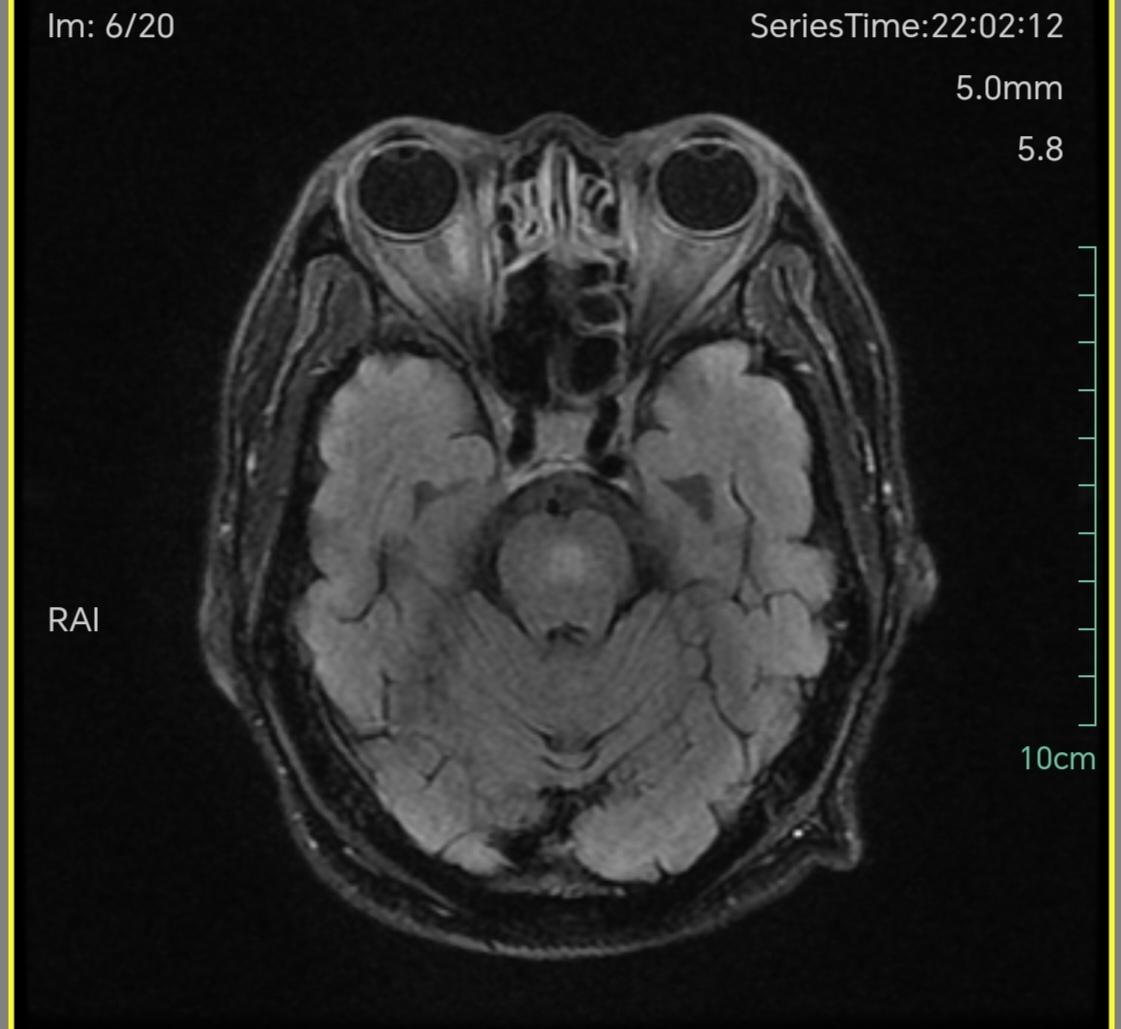

三叉戟🔱征。三叉戟征(Trident sign)是脑桥中央髓鞘溶解症较为典型的影像学表现,其形成的原因主要与该部位的解剖结构相关。中脑大脑脚的皮质脑桥纤维终止于脑桥核,这些细胞的轴突发出脑桥横行纤维,后者越过中线与皮质脊髓束和皮质核束交叉,并将其分成许多小束。脑桥横行纤维进入小脑中脚,分布于小脑半球。当这些部位的髓鞘溶解时,就可形成三叉戟征。